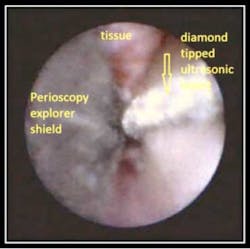

by Dr. John Y. Kwan The below pictures and corresponding video show a tooth with an enamel projection which has developed bone loss. In the video “Enamel Projection,” a Satelec diamond tip was made Magnetostrictive by the Tony Riso Co. and is used to remove the projection and clean into the furcation.

Photo 2 Photo #1 identifies the enamel projection. Photo #2 shows the curved unltrasonic insert removing the projection and cleaning into the furcation.

As the above picture demonstrates, the enamel projection has been removed and the furcation is now clean and clearly defined post instrumentation.

Prior to the Perioscopy System, this area would have required surgical intervention to view and treat.